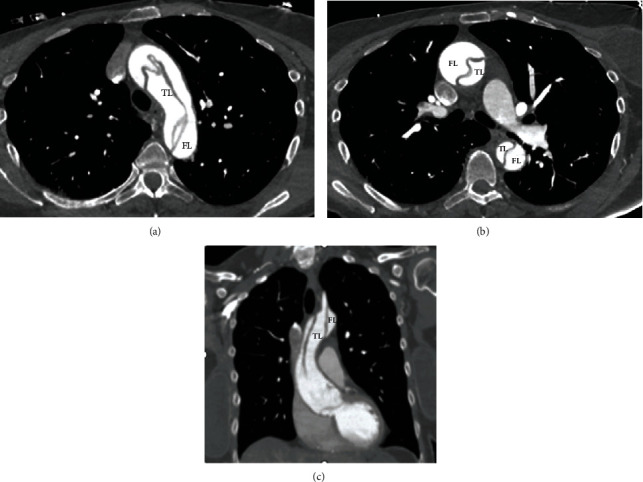

Background: Aortic dissection (AD) is a rare but serious medical emergency where the aorta's inner layer tears. Females are less likely to develop it than males, and AD cases with unusual symptoms can be hard to diagnose. Diagnosing AD can be further complicated as its symptoms and electrocardiogram (ECG) changes can mimic acute coronary syndrome, and it is challenging to distinguish it without risk factors. Case Report. This case report describes a 60-year-old female patient who presented with unusual symptoms, including pain in her chest, neck, left arm, and lower extremities. An electrocardiogram (ECG) revealed ST elevation in leads aVR and V1, as well as severe ST depression and T wave inversion in the inferior and lateral leads, which can mimic acute coronary syndrome. Despite initial treatment with nitroglycerin, the patient's pain worsened, and a CT angiography revealed type A aortic dissection extending from the aortic root to the right external iliac artery. Immediate surgery was recommended, which significantly improved the patient's condition.